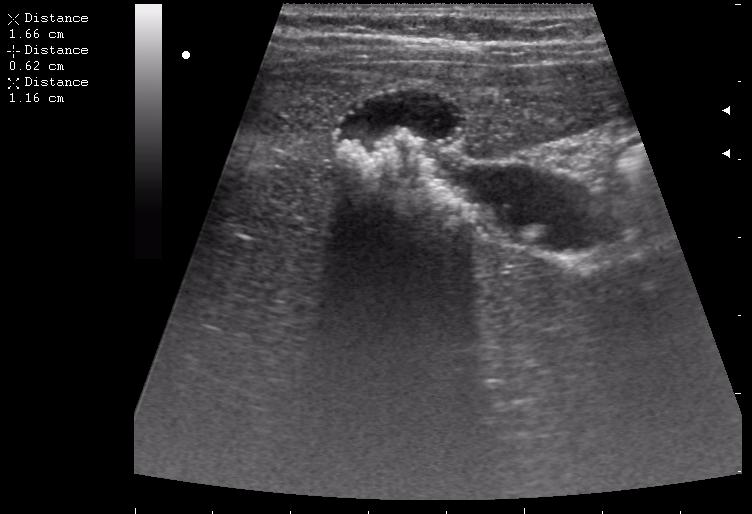

наезд большой черной Прады на маленькую (13кг) 5-летнюю девочку.

получает Медаксон, рабочая версия - изменение желчного пузыря вследствии травмы (шепотом - рекомендация хирургу сменить антибиотик)